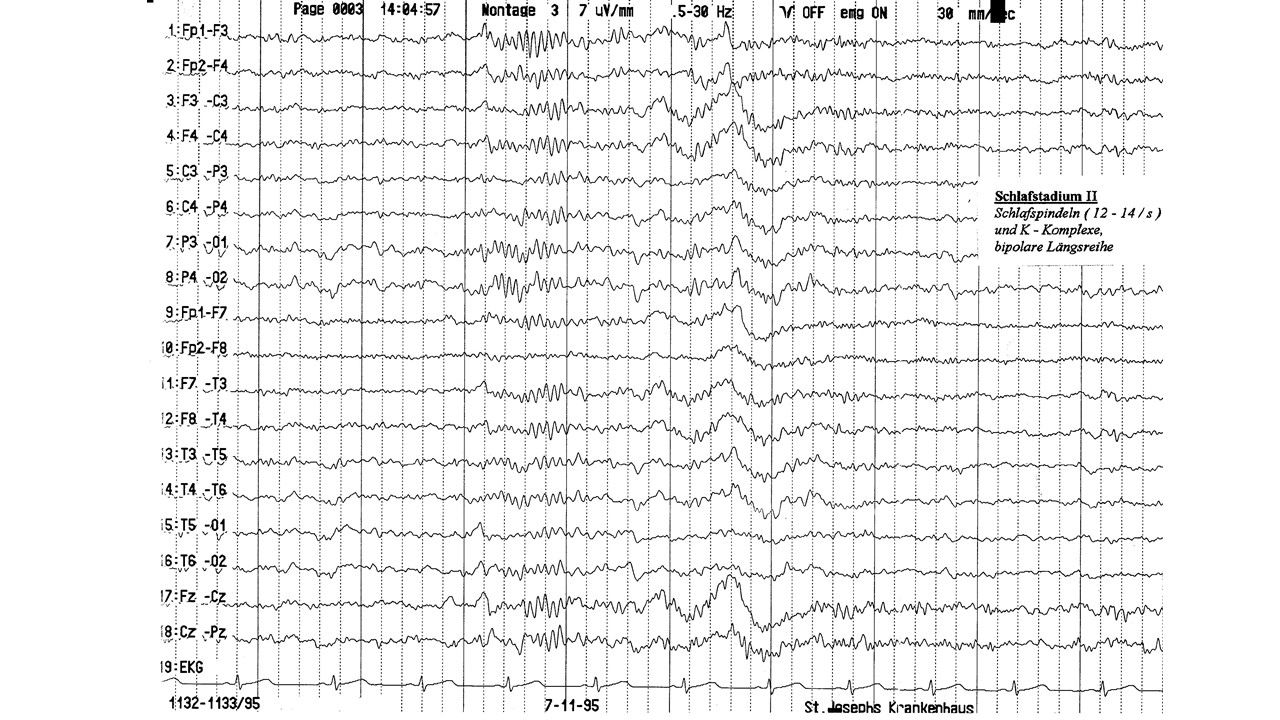

folie90.jpg